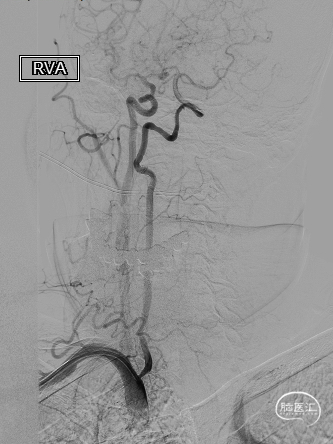

长SIM与6F导引导管同轴,泥鳅导丝引导下将6F导引导管送至颈总动脉远端(左图),保护伞到位(右图)。

4.0*30mm通桥白驹®球囊以6atm扩张(左图箭头),扩张完毕后多角度造影显示狭窄交前明显改善(中图箭头处),扩张完毕后支架置入(右图箭头处)。